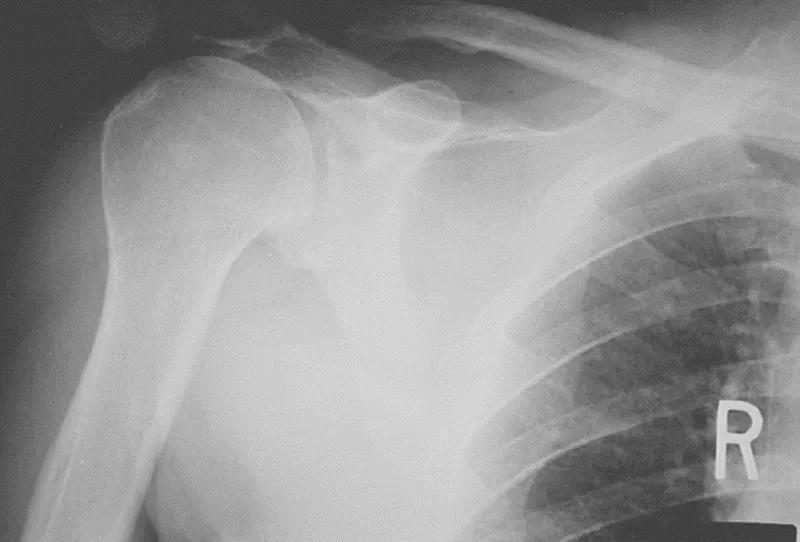

三、影像学检查1、X线检查X线检查用来评估肩峰形态,肱骨头和肩盂的关系,以及除外其他疾病。

图16 巨大肩袖损伤,肩峰下间隙<9mm